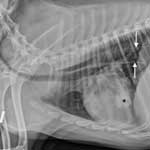

- Диагноз. Диагноз на пневмонию ветеринарный специалист клиники ставит комплексно на основании симптомов болезни, проведения лабораторного исследования крови и мочи. Общий анализ крови дает нейтрофильный лейкоцитоз с сдвигом влево, количество эритроцитов и гемоглобина уменьшается. В обязательном порядке больной собаке делается рентгенография и рентгеноскопия легких, на рентгенограмме видны участки затемнения. Рентгенологическое обследование грудной клетки должно проводиться в двух проекциях. Для исключения пневмоний паразитарного происхождения проводят исследование кала на гельминты.

Назначается рентгенографическое обследование для определения степени поражения лёгочной ткани, повторно этот вид диагностики проводят для проверки эффективности проводимого лечения.

Во-первых, специалисты сделают рентген. Это поможет выяснить, какие доли легких поражены, насколько далеко зашел процесс. Кроме того, обязательно требуется анализ крови. Это помогает подтвердить или опровергнуть наличие локализованного, серьезного воспаления в организме животного. Наконец, именно результаты гематологического исследования могут указать на конкретную причину болезни.